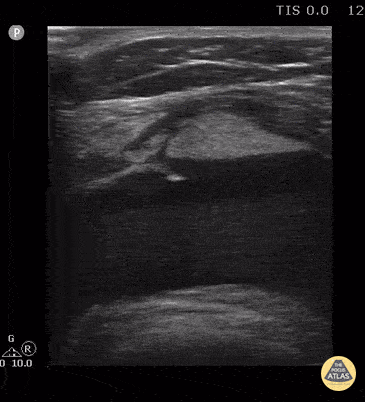

This is the short axis view of the case series. 15 year old female with patella fracture after a fall. Note the large suprapatellar effusion with discrete layering of the echogenic marrow/adipose above the acute hypoechoic blood. The lipohemarthrosis is visible in long and short axis. Contributor: Antonio Riera, MD Yale University School of Medicine